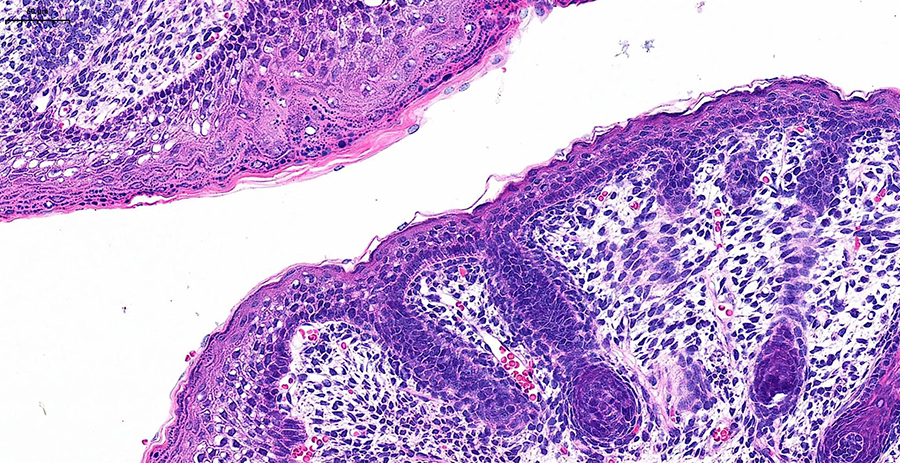

Погрузитесь в будущее гистологической лаборатории на двухдневном мероприятии, где представится возможность поработать с новейшим гистосканером LG-S80 от Servicebio.Погрузитесь в будущее гистологической лаборатории на двухдневном мероприятии, где представится возможность поработать с новейшим гистосканером LG-S80 от Servicebio.

Сможете оценить высочайшее разрешение, скорость обработки (полное стекло за 3-5 минут) и интеллектуальное аналитическое ПО, которое автоматически распознаёт структуры и формирует количественные отчёты с готовыми данными. Можно принести для апробации свои образцы, демонстрируемая конфигурация флуоресцентных каналов (Ex/Em, нм):